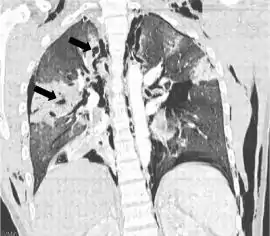

![]() TC coronal que muestra radiolucencias (áreas pálidas en la radiografía) en el pulmón causadas por laceraciones pulmonares ubicadas a la izquierda de la imagen (flechas negras) | ||

La laceración pulmonar puede no ser visible utilizando radiografía de tórax porque una contusión pulmonar asociada o hemorragia lo puede ocultar. Cuando la contusión pulmonar aclara (normalmente dentro dos a cuatro días), las laceraciones comienzan a ser visibles en la radiografía de tórax.[14] Una TAC es mejor detectando laceraciones pulmonares que una radiografía de tórax,[15] y a menudo revelan múltiples laceraciones en casos donde radiografía de pecho mostró solo un contusión. Antes de que las TAC estuvieran disponibles masivamente, la laceración pulmonar era considerada poco usual debido a que no era común encontrarlas en las radiografías. En una TAC las laceraciones pulmonares aparecen en un área contusa del pulmón,[16] típicamente apareciendo como las cavidades llenas de aire o fluido[17] que normalmente tener una forma circular u ovoide debido a la elasticidad del pulmón.